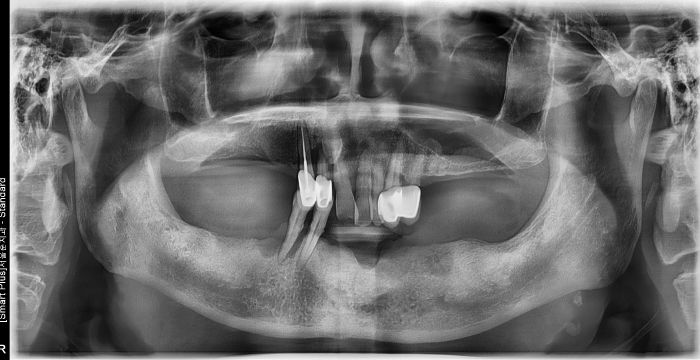

즉시 식립 임플란트 전후 사례

• 식립 전

식립 후

식립 전